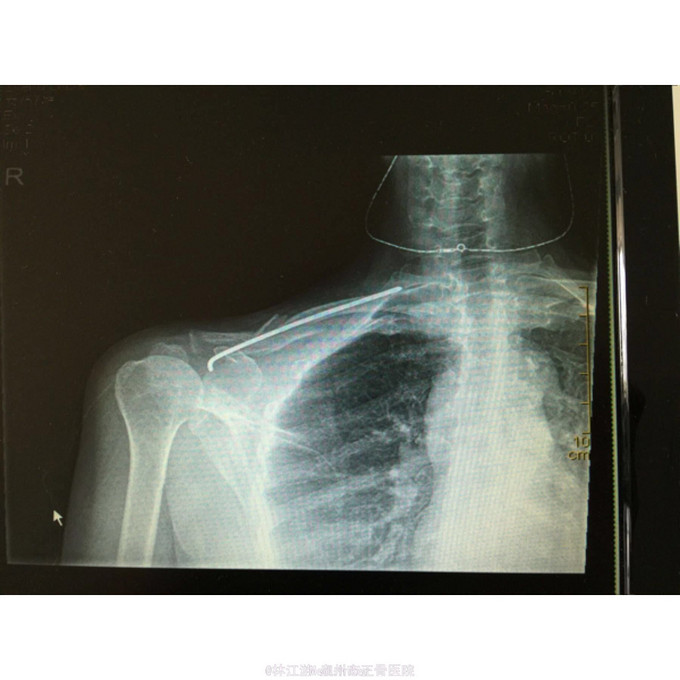

右锁骨粉碎性骨折闭合复位克氏针内固定术

右锁骨粉碎性骨折 行闭合复位克氏针内固定术

术后三年取内固定物,肢体活动正常